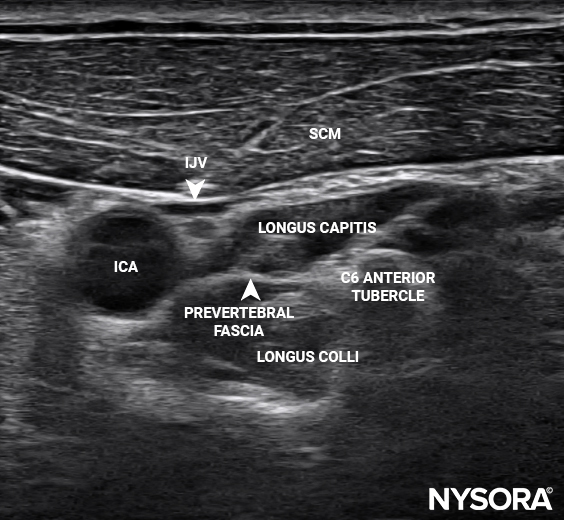

• Clear guidance on anatomical landmarks and sonoanatomy

• High-resolution clinical and ultrasound images